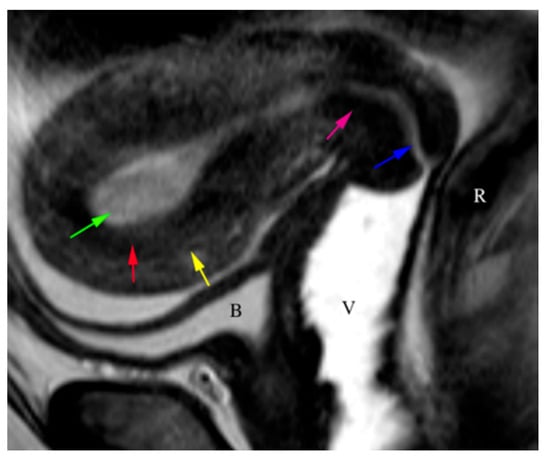

5.3. Magnetic Resonance Imaging (MRI)

- Maheshwari, E.; Nougaret, S.; Stein, E.B.; Rauch, G.M.; Hwang, K.-P.; Stafford, R.J.; Klopp, A.H.; Soliman, P.T.; Maturen, K.E.; Rockall, A.G.; et al. Update on MRI in Evaluation and Treatment of Endometrial Cancer. RadioGraphics 2022, 42, 2112–2130. [Google Scholar] [CrossRef] [PubMed]

- Nougaret, S.; Horta, M.; Sala, E.; Lakhman, Y.; Thomassin-Naggara, I.; Kido, A.; Masselli, G.; Bharwani, N.; Sadowski, E.; Ertmer, A.; et al. Endometrial Cancer MRI staging: Updated Guidelines of the European Society of Urogenital Radiology. Eur. Radiol. 2019, 29, 792–805. [Google Scholar] [CrossRef]